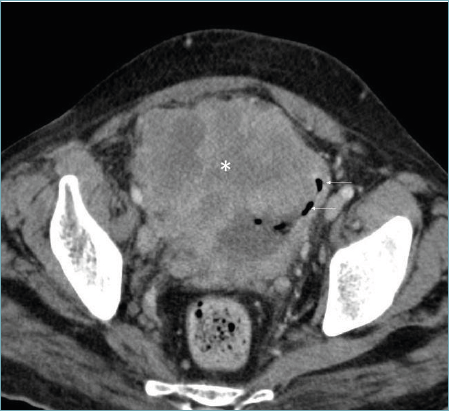

Figure 3. Axial CT study shows a proliferative partly exophytic heterogeneously enhancing mass (*) arising from the urinary bladder. Few air specks are seen in the urinary bladder (arrows), likely post catheterization.